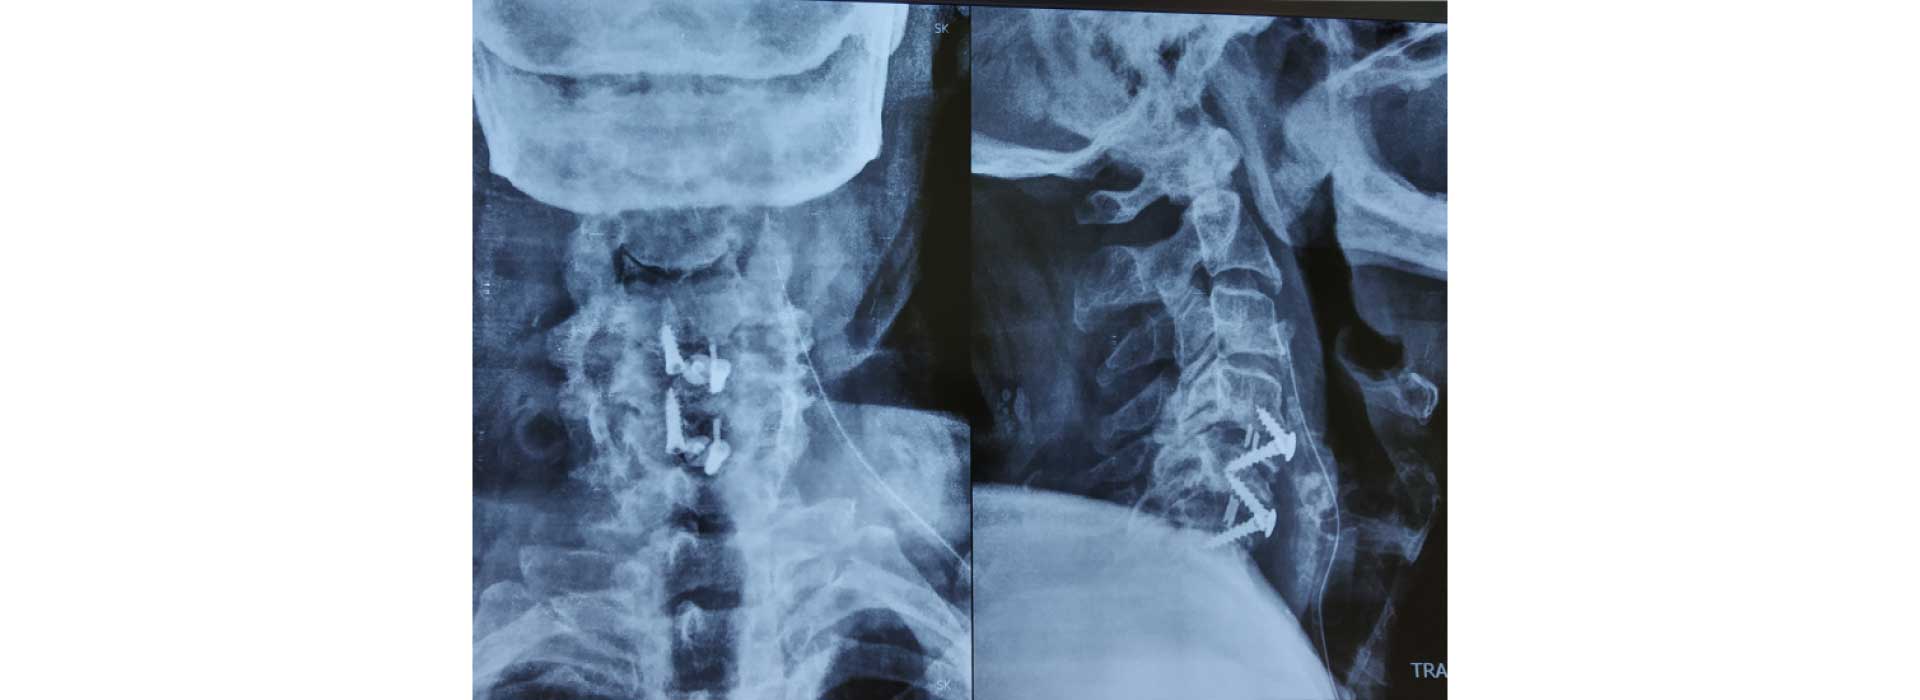

All kind of simple and complex surgery for cervical, dorsal and lumbar spine